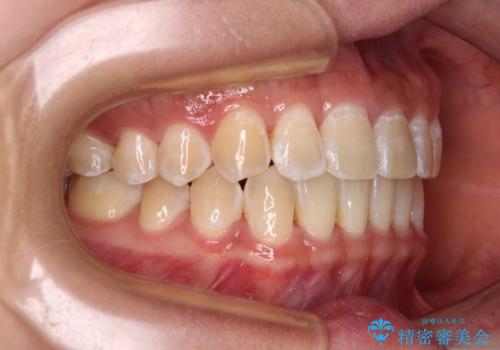

前歯の隙間と上下正中のズレを解消

- 上下前歯隙間と正中のズレを改善したいとのことで来院された患者様です。

自己管理を減らしたいとのことで、ワイヤー装置による矯正治療を行うこととしました。

正中がなかなか合わずに、2年近くの治療期間を要しました。